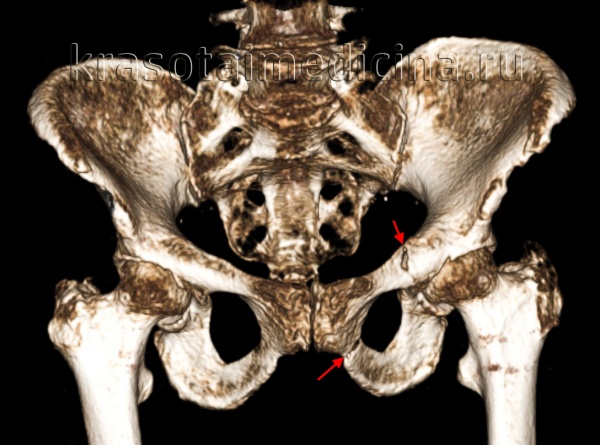

Перелом ветви лобковой кости — это наиболее часто встречающийся перелом таза, причем верхняя ветвь поражается чаще нижней. Перелом правой лобковой кости — второй по частоте среди переломов костей таза, верхняя половина кости повреждается чаще нижней. Переломы лобковой кости и ее ветвей составляют 70% всех переломов таза. Частота переломов остальных костей таза по нисходящей следующая: правая подвздошная кость, левая подвздошная кость, седалищная кость, левая вертлужная впадина и правая вертлужная впадина. Крестцово-подвздошные переломы сопровождаются наиболее значительным кровотечением. Больным с массивным кровотечением при переломе таза может потребоваться хирургическое вмешательство.